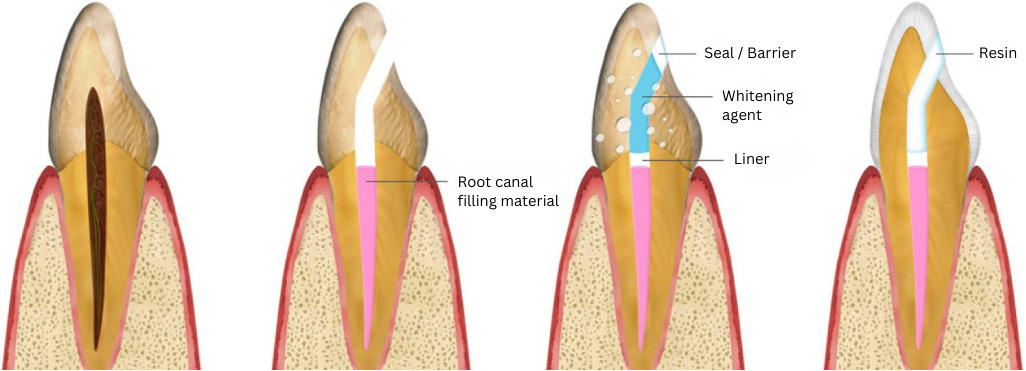

How Does Non-Vital Whitening Work?

In the case of a necrotic tooth, since the iron component of hemoglobin has penetrated into the mineral crystals of the teeth and changed their color, if we remove the discolored pulp (nerve) and replace it with a tooth whitening agent (sodium perborate component), the teeth will be whitened and appearance greatly improved.

Step 1

The dentist creates a small access hole into the tooth and removes the dead pulp. The the root canal filling material is sealed with a protective liner.

Step 2

The tooth is filled with a whitening agent that is temporarily sealed and left for days or weeks to bleach the inside of the tooth. This may be repeated to achieve the desired result.

Step 3

The whitening agent is removed, and the tooth is permanently filled and sealed with resin to protect the inside of the tooth and prevent further internal discoloration.

* In cases where the pulp has dried out, non-vital tooth whitening may not be possible. Please consult with a doctor to find out the viability of non-vital tooth whitening.